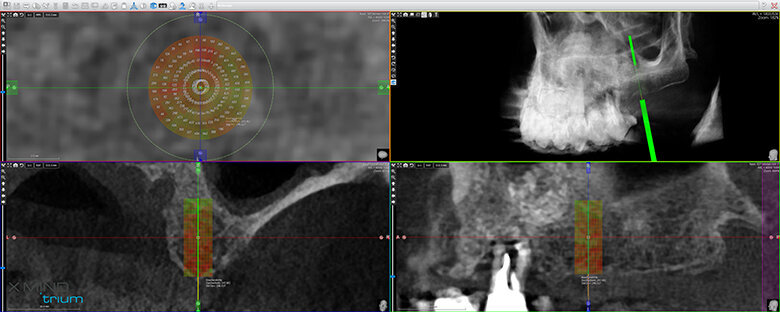

Figure 1 shows a split-mouth case with a bilateral INTRALIFT procedure: after a small crestal “booklet”-flap of approx. 7x7mm is detached, the sinus floor is safely opened with ultrasound Piezotome tips (Figs. 2 & 3), the sinus membrane then detached by the hydrodynamic cavitation effect of the Piezotome-tip TKW5 plugged into the approach canal (Figs. 4 & 5) and the subantral scaffold filled with 2cm of randomly assigned biomaterial (Figs. 6 & 7), followed by wound closure (Fig. 8). After a mean healing period of 8,4 months X-Mind trium CBCT scans were performed, the digital setup of the future bridge constructed with the AIS 3D app and the bone density determined in the sinus-lift site around a virtual implant (Fig. 9). Standardised implants (4mm in diameter and 12mm in length) were then inserted in the position of the virtual implant and insertion torque values (ITV) measured intra-surgically (test groups; Fig. 10). A total of 27 patients with sufficient native subantral crestal bone (min. crest width: 6 mm, height: 12 mm) were screened by X-Mind trium CBCT for bone density with the virtual implant (Fig. 11), the standardised implant inserted and the ITV recorded (control group). Figure 12 depicts the final result after implant insertion in the patient case shown in Figures 1–9.

As can be seen in Fig. 13, the mean CBCT bone density values in Hounsfield units (HU) at the implant site differed significantly (p <0.05) between all four test groups and the control group. The precise numerical HU values are “translated” by AIS 3D app software and are also colour-coded for easier interpretation at first glance: the brighter the green the CBCT voxel matrix shows around the virtual implant, the higher the bone density, with a virtual neutral threshold of 500 HU. Contrary, the more reddish the CBCT voxel matrix around the digital implant is depicted, the worse the biomechanical bone quality (Fig. 14). The corresponding insertion torque values (ITV) of the inserted standardised implant measured at the location of the transcrestal INTRALIFT approach (Fig. 2) also differed significantly between all test groups and the control group. Figure 15 depicts the cumulative result of the correlation between HU and ITV values for all test groups and the control group.